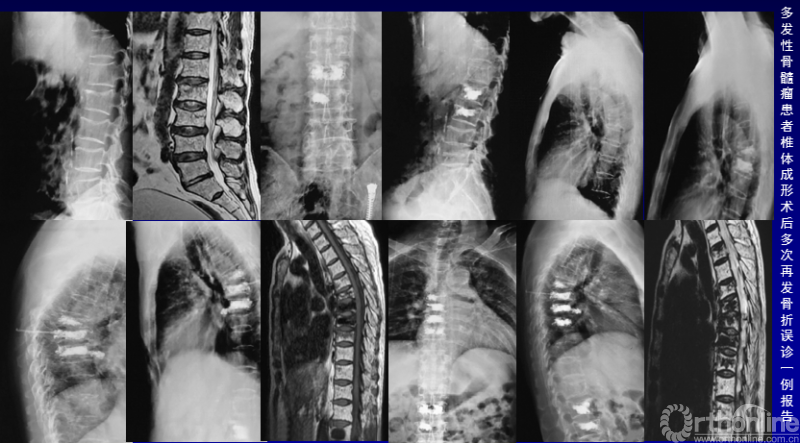

病例赏析:

原发性骨质疏松症可通过临床表现、影像学表现、骨量减少等诊断,在此要除外继发性骨质疏松,如低磷性骨软化症、甲状旁腺功能亢进症、多发性骨髓瘤、骨转移瘤等。文献报道术前诊断OVCFs,术后病理回报恶性肿瘤发生率为0.7%~7.3%,需要特别注意。